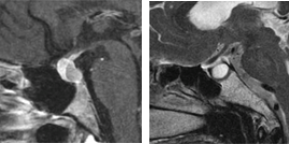

下垂体腺腫内視鏡単独経鼻的アプローチ

下垂体腺腫に対して内視鏡単独で経鼻的アプローチにより摘出術を施行。耳鼻科医と合同で行っている。(左)術中および術後MRIの所見。腫瘍被膜上に造影病変が認められているが、術後MRIでは消失している。術中MRI画像をナビゲーション用にアップデートし、残存腫瘍の摘出操作の際に役立てている。